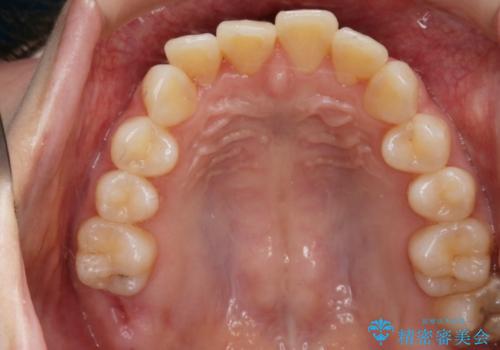

- 笑った時の歯の見え方を治したいとのことで矯正相談にいらっしゃいました。

一見そこまで大きなガタつきはないようにも見えますが、前歯の角度の不揃いや噛み合わせのズレなどから見え方に影響が出てしまっていました。

抜歯は全く必要のないレベルのガタつきだったため、マイクロインプラントを用いて歯全体を後方に移動させていくことできれいな歯並びを獲得することができました。